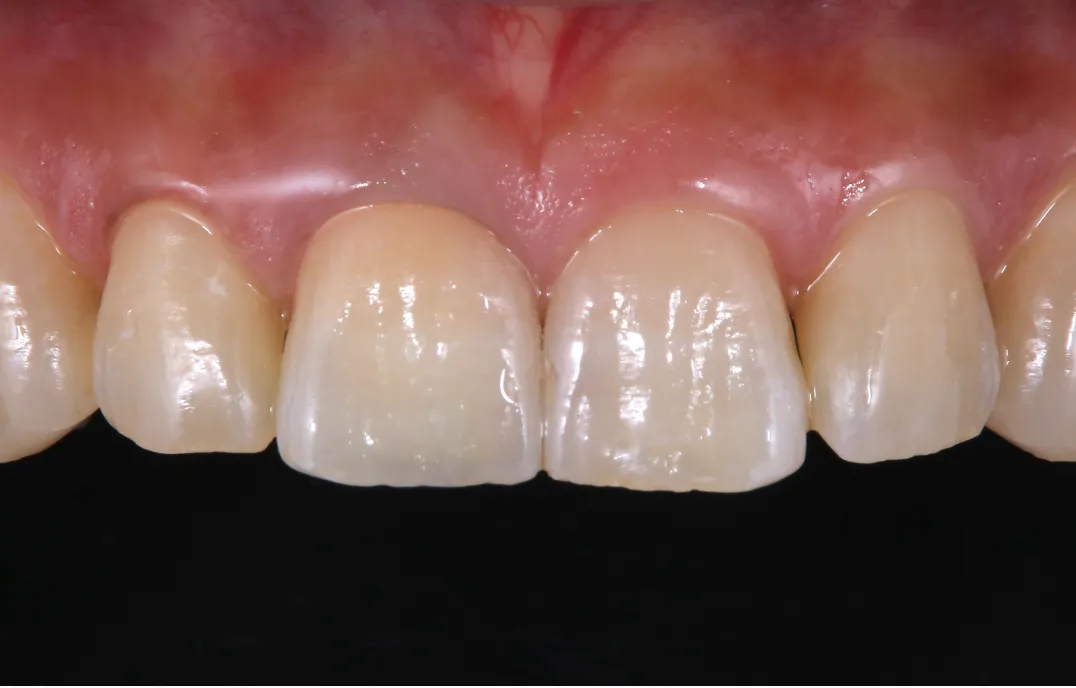

●金属フレームを使用した被せ物の使用を避ける

●被せ物と歯の隙間が空かないように精度の高い治療を行う

仮歯期間が終了し、最終的なセラミックの被せ物が入れば、歯茎の黒ずみが改善するだけでなく、自然な見た目を実現することができます。 当院ではセラミックの再治療を専門的に行っており、 被せ物と歯の隙間が空かないように精度の高い形態のセラミックの被せ物を作製いたします。